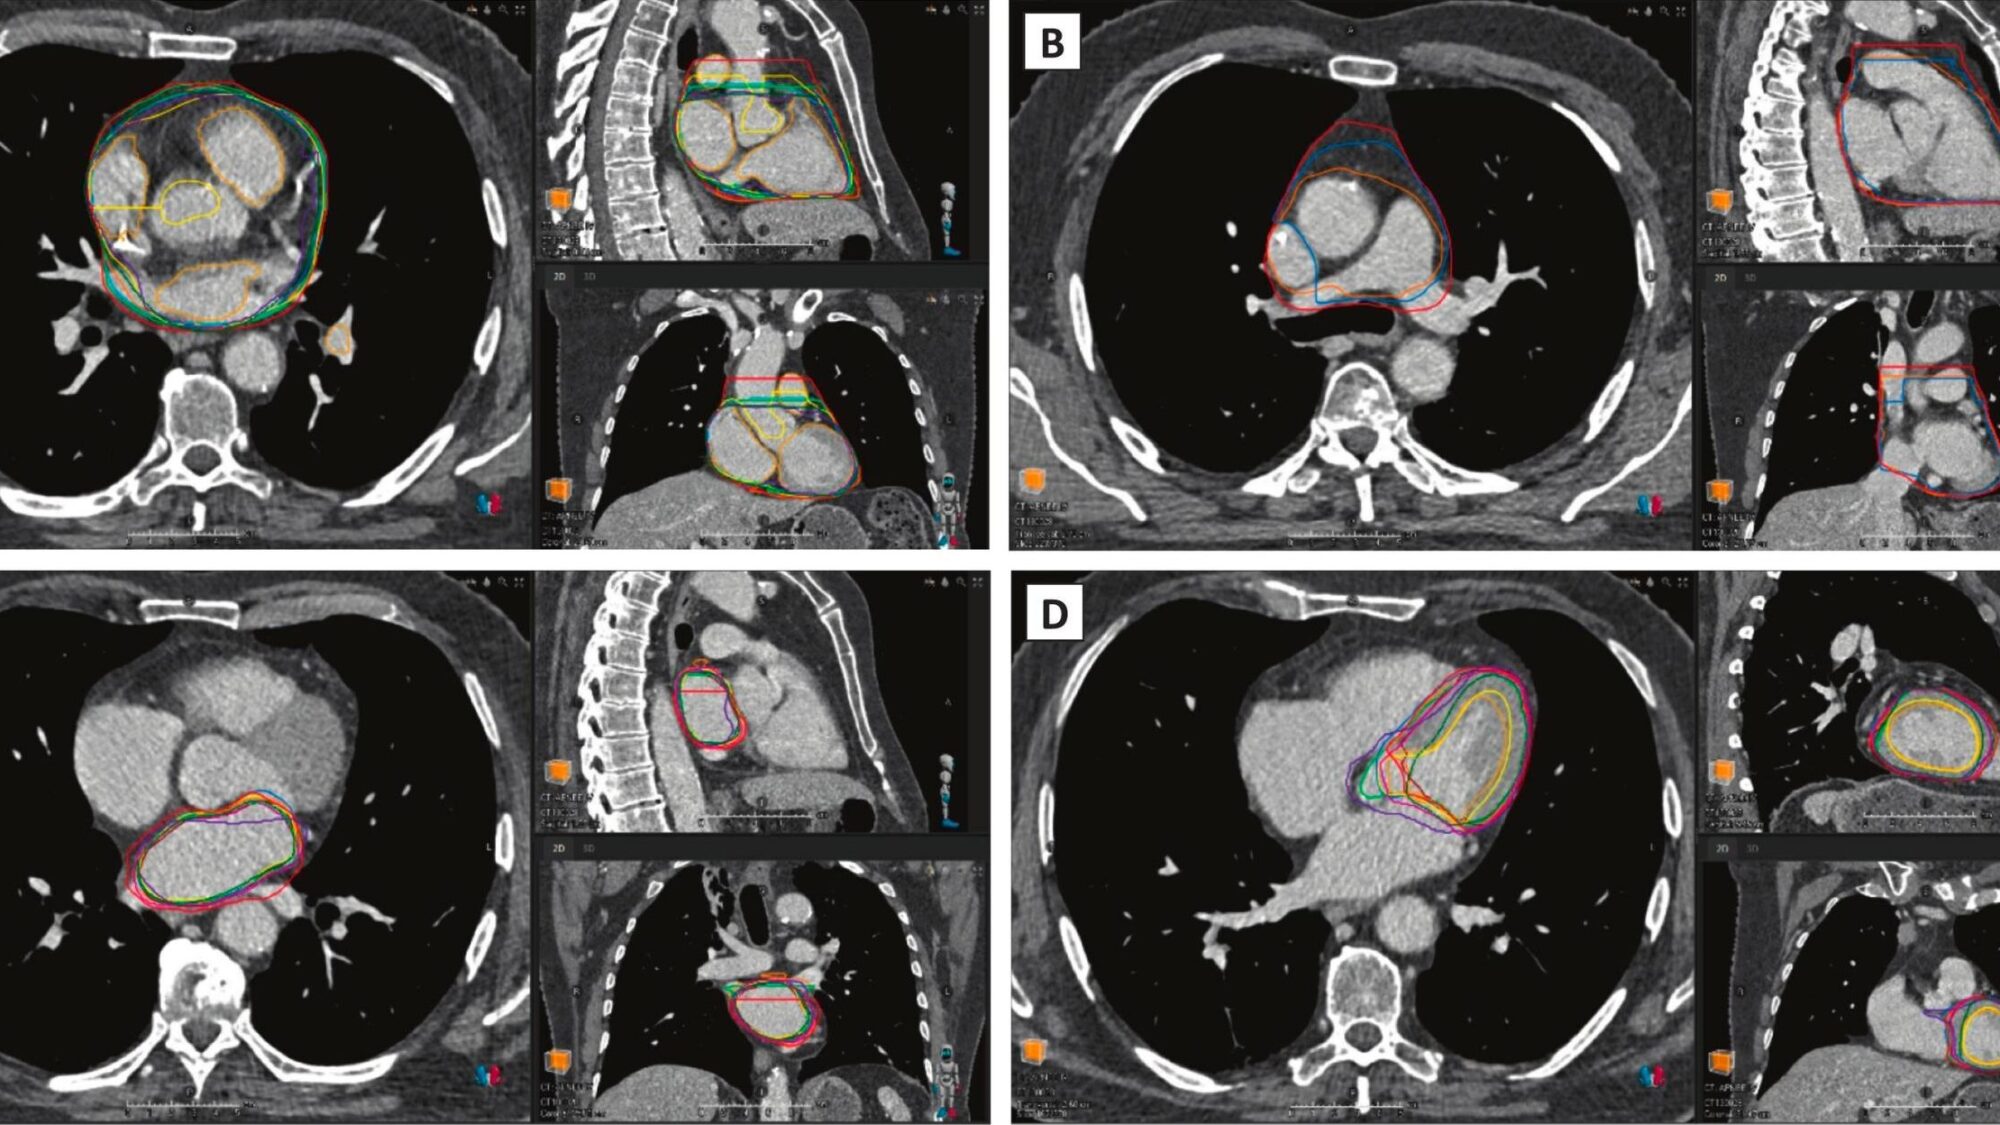

En radiothérapie, les outils de contouring basés sur l’intelligence artificielle permettent de délimiter automatiquement les organes sur les examens de scanner. Ces outils promettent une évaluation des doses reçues par les structures cardiaques, au-delà de la dose cardiaque moyenne. Une étude parue dans la revue phiRO [1] et réalisée par des chercheurs du département d’oncologie radiothérapeutique de l'Institut de cancérologie de l’ouest, à Saint-Herblain (44), a analysé les variations des contours du cœur selon les logiciels utilisés et évalué l’impact de l’absence de contraste sur la performance du contouring pour chaque solution. « Cette étude ne visait pas à classer les solutions [...] mais plutôt à fournir un retour sur les variations observées, qui pourraient guider les améliorations futures du modèle », précisent les auteurs dans leur article.

Les chercheurs ont comparé onze solutions d’auto-contourage basées sur l’IA, sept commerciales, t